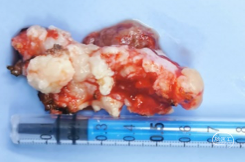

病理诊断

砂砾型脑膜瘤,WHO 1级。